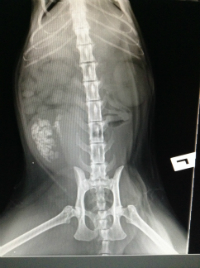

An x-ray was also taken and confirmed that this was indeed the case... read on to find out more about Molly’s case and also to find out more about feline lower urinary tract disease (FLUTD) and how it can be treated.

Molly presented to Mosman Vet for weight loss and for being a little bit fussier with her food. With these general signs, we ran a full blood profile to check her kidney function, sugar levels (to rule out diabetes mellitus) and general health status. All these parameters were within the normal ranges for an older cat and so we then scheduled an abdominal ultrasound. This is where we discovered what was affecting Molly… she had bladder stones!